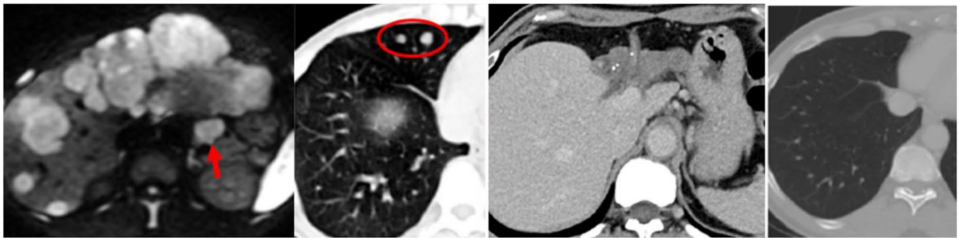

7例疾病稳定(SD)患者中42.9%术后未复发,中位OS达45个月,提示即使未达影像学缓解,HAIC仍可能改变肿瘤生物学行为。图1展示的Vp4患者经3周期HAIC后实现PR,术后5年无复发;图6则证实HAIC对肺转移灶的全身控制作用。